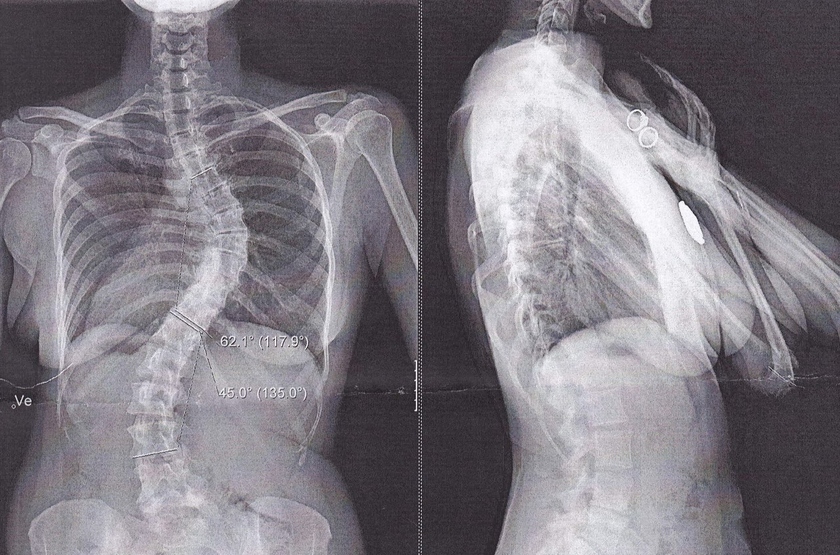

Сколиоз 4 степени.

Четвертая степень сколиоза. Наблюдается очень сильное искривление таза и туловища, выраженные задний и передний горбы.